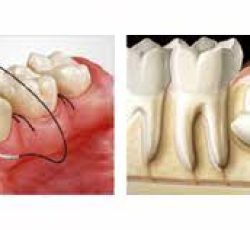

1 – Extração do siso -retirada dos terceiros molares, popularmente conhecidos como dentes do juízo ou dentes do siso.

3 – Cirurgia oral menor – extração dentária, na qual o profissional aplica anestesia local e remove a dentição comprometida de forma rápida e segura, evitando que maiores problemas surjam na cavidade e coloquem a saúde bucal em risco.